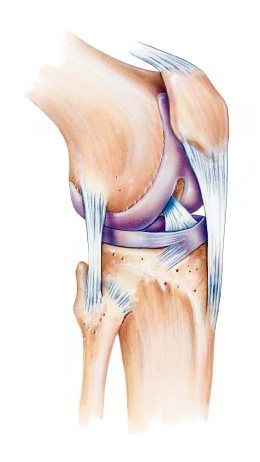

Kniescheibe mit

Bändern, Schema Seitenansicht Kniescheibe mit Bändern, Schema Seitenansicht [2] und von vorn [3]

-- die Kniescheibe ist eine etwas dreieckige Scheibe mit Wölbung zum Schutz des Knies

-- die Kniescheibe wird von Sehnen oben und unten gehalten, oben am Oberschenkelmuskel angesetzt, unten am Schienbein angesetzt

-- dank der Kniescheibe und den Sehnen kann man das Bein in leichter Weise strecken

-- die Rückseite der Kniescheibe hat eine Knorpelschicht für das Gleiten beim Beugen und Strecken des Beines

-- im Alter bildet sich die Knorpelschicht zurück, so beginnt oft eine Kniearthrose

-- Schäden an der Kniescheibe können sein: Fehlbildung, Bruch, Entzündung [web01]

Schema Knie Querschnitt

Knie Schema mit dem Querschnitt [x1]

"Die Kniescheibe (Patella) ist ein flacher Knochen, der vor dem Kniegelenk liegt. Von vorne betrachtet hat die scheibenförmige Kniescheibe eine eher dreieckige Form mit einer leichten Wölbung nach vorn. Die Kniescheibe ist in die Sehne eingebunden, die am Oberschenkelmuskel ansetzt. Sie vergrößert damit die Hebelwirkung der Sehne und sorgt dafür, dass wir das Bein mit geringem Kraftaufwand des Oberschenkelmuskels strecken können. Außerdem schützt sie das Kniegelenk. Wenn wir das Knie strecken und wieder beugen, wandert die Kniescheibe mehrere Zentimeter über den Oberschenkelknochen. Deshalb ist die Rückseite der Kniescheibe mit einer dicken Knorpelschicht überzogen. Schäden an der Kniescheibe können sich aus Fehlbildungen ergeben, durch Bruch oder Entzündungen entstehen. Außerdem beginnt eine Kniearthrose häufig an der Kniescheibe." [web01]